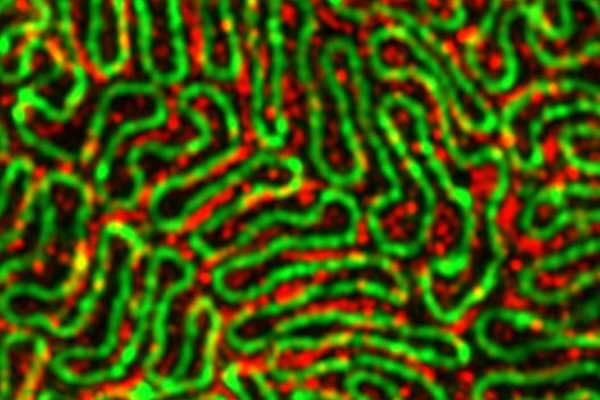

Super-resolution microscopy is revealing unprecedented insight into the protein structures that underlie the stability and function of the kidney filtration system. The new grant to the Miner, Genin and Suleiman labs will transform these insights into potential targets for the treatment of kidney disease. (Photo credit: Dr. Pongpratch Puapatanakul, MD, laboratory of Jeff Miner)

The project leverages expertise across disciplines, with Miner's lab providing knowledge of kidney biology, Suleiman bringing expertise in advanced imaging techniques and cell biology, and Genin contributing knowledge of mechanical forces in living systems. The team will use state-of-the-art imaging, including super-resolution microscopy, to visualize podocyte structure in unprecedented detail. They will also employ techniques to measure and manipulate the mechanical forces on cells.